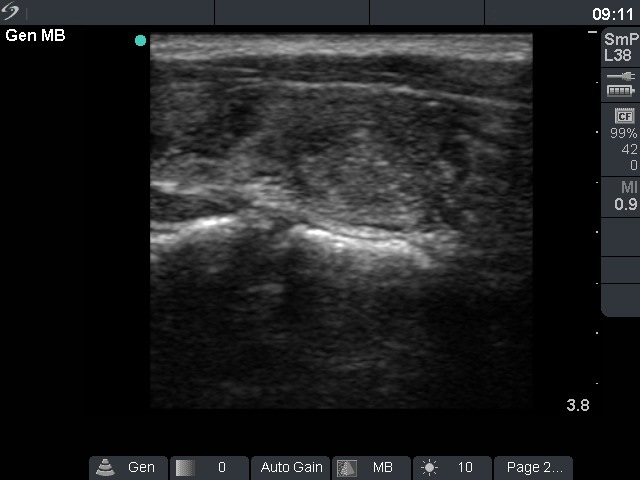

Benign hyperplastic nodules (histological diagnosis) - case cons 024 |

The larger lesion has a solitary bright figure which shape stands for a comet-tail artifact.

There are pale lines and granules within the nodule - these figures correspond to a connective tissue. The three granules are probably also presentations of a connective tissue.